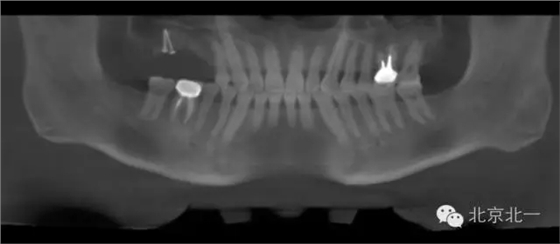

圖十九:手術后當天CBCT

圖二十-二十二:ONLAY植骨半年后